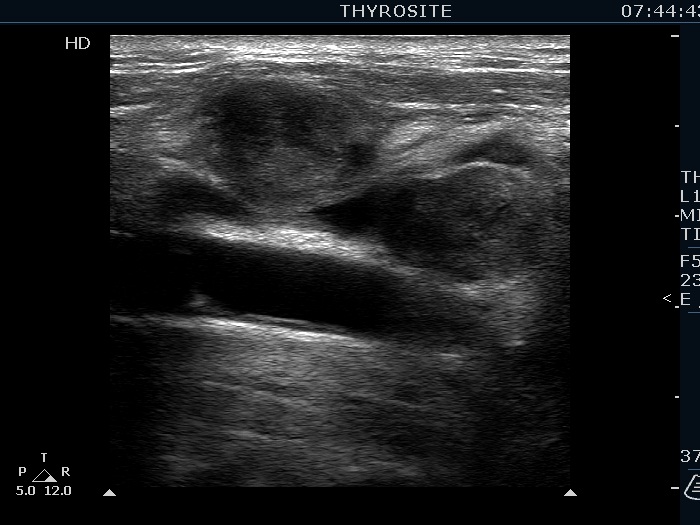

Ultrasonography. The right lobe was echonormal and presented several hypoechoic nodules. A large, inhomogeneous, partly deeply hypoechoic, partly minimally hypoechoic or echonormal mass occupied the left lobe. The borders of the tumor were irregular. There were multiple lymph nodules upper and lateral to the left thyroid lobe. The nodes had a heterogeneous pattern and lacked hilum. The vascularity was scanty both in the thyroid nodules and the lymph nodes.